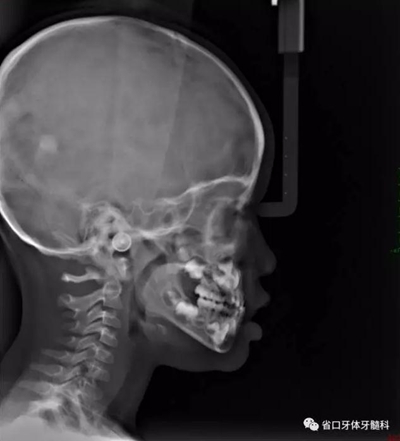

10.jpg

圖10 側位片